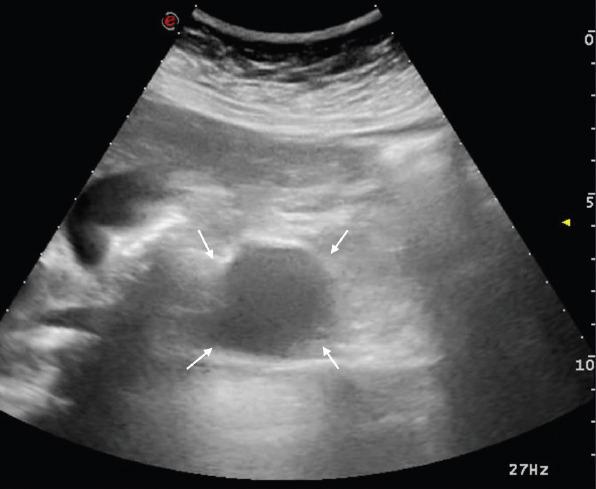

Agenesis of the dorsal pancreas (ADP) is extremely rare disease with no specific symptoms and there is no clear pathogenesis. Approximately half of the affected individuals develop diabetes resulting from reduced islet cell mass secondary to lack of endocrine structures. In this case, we aimed to present a 17-year-old female patient with ADP accompanied by a pancreatic cyst.

背侧胰腺发育不全(ADP)是一种极为罕见的疾病,没有特定症状,发病机制也不明确。大约一半的患者会因内分泌结构缺失导致胰岛细胞数量减少而患上糖尿病。在此病例中,我们旨在介绍一名17岁患有ADP并伴有胰腺囊肿的女性患者。